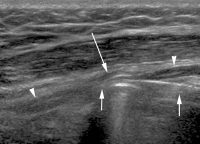

Abbildung 1a-b: Sonographischer Transversalschnitt (a) und Plastinationsschnitt (b) durch ein anatomisches Handgelenkspräparat mit Darstellung des Nervus medianus. In der Korrelation zeigt sich der Aufbau des Nervs aus mehreren Faszikelgruppen (Pfeile), welche durch echoreiches epineurales Gewebe voneinander getrennt und durch eine äußeres Epineurium (Pfeilspitzen) gegen die Umgebung abgegrenzt sind. FS: Flexorensehnen, PQM: Pronator quadratus-Muskel.

Abbildung 2: Sonographischer Längsschnitt durch den Nervus medianus (Pfeile) am distalen Unterarm eines Probanden mit Darstellung der typischen longitudinal verlaufenden, durch echoreiches Epineurium gegliederten, hypoechogenen Faszikelgruppen. Im Gegensatz dazu diskontinuierliche, eher echoreiche Faszikel der Beugesehnen (Pfeilspitzen).